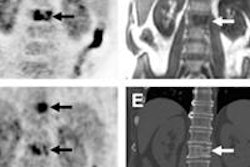

The company said its ongoing phase II clinical trial of CardioPET for the assessment of coronary artery disease has shown positive results. Data were presented on February 6 at the Society of Nuclear Medicine and Molecular Imaging (SNMMI) Mid-Winter Meeting in Palm Springs, CA.

The results are encouraging for fatty acid imaging, presenter and study author Dr. Fabian Demeure said in a statement. CardioPET was well-tolerated and safely administered at Université Catholique de Louvain in Belgium, where part of the multicenter trial is being performed.

In addition, the agent showed rapid blood clearance with excellent image quality, and image time was within three minutes of injection, Demeure said.